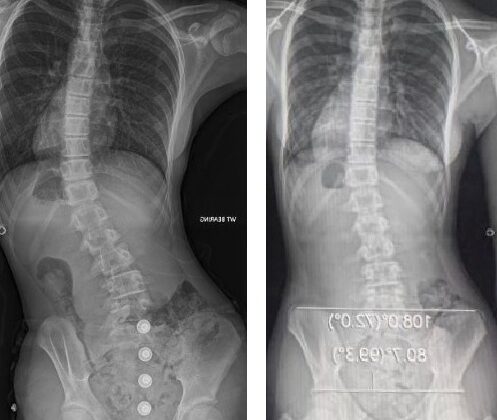

يعاني بعض الأطفال والمراهقين من حالة تُعرف باسم اعوجاج العمود الفقري مجهول السبب لدى المراهقين، وهي انحناء جانبي في العمود الفقري يظهر غالبًا خلال فترة النمو السريع. من أكثر طرق العلاج شيوعًا في المراحل المتوسطة من المرض هو استخدام الجبيرة الطبية (Brace). لكن السؤال الذي يشغل بال كل أسرة هو: هل ستنجح الجبيرة فعلًا في إيقاف تطوّر الانحناء؟

معدل التصحيح الأولي هو النسبة المئوية للتحسّن الذي يظهر في زاوية انحناء العمود الفقري فور ارتداء حزام اعوجاج العمود الفقري لأول مرة.

بمعنى آخر، يقيس الأطباء مقدار استجابة العمود الفقري للجبيرة في الأيام أو الأسابيع الأولى من العلاج.

في دراسة شملت ما يقارب 500 مراهق خضعوا للعلاج بحزام اعوجاج العمود الفقري وتابعهم الأطباء لأكثر من عامين، لاحظ الباحثون أن:

الأطفال الذين حققوا تحسّنًا أوليًا بنسبة 50% أو أكثر كانت لديهم فرصة أعلى بكثير لنجاح العلاج.

أما الذين كانت استجابتهم الأولية أقل من ذلك، فكانوا أكثر عرضة لتقدّم الانحناء رغم ارتداء حزام اعوجاج العمود الفقري.

غالبًا يتم قياسه بعد فترة قصيرة من بدء ارتداء الجبيرة، من خلال أشعة سينية تُظهر الفرق بين زاوية الانحناء قبل وبعد الجبيرة.

إذا كان هذا المعدل 50% أو أكثر، فغالبًا ما تكون فرص النجاح عالية في السيطرة على الانحناء ومنع تفاقمه. أما إذا كان أقل، فهو جرس إنذار مبكر لمراجعة الخطة العلاجية وتعزيز المتابعة.